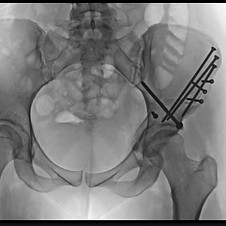

HIP/PELVIS INJURIES AND TREATMENTS